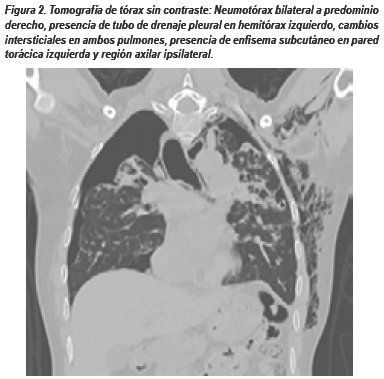

PRESENTACIÓN DEL CASO

Paciente varón de 42 años natural y procedente de Lima, sin antecedentes médicos de importancia, con diagnóstico de Meduloblastoma Cerebeloso operado en el 2005 (craneotomía suboccipital izquierda + resección total de tumor), recibió adyuvancia con radioterapia y quimioterapia la cual consistió en 10 cursos de Carmustina (BCNU)yVincristina con regular tolerancia. Acude a control en Agosto 2016, refirió tiempo de enfermedad de 3 meses caracterizado por disnea a grandes esfuerzos la cual empeora súbitamente en la última semana. Al examen físico: paciente hemodinámicamente estable, taquicárdico, saturación de oxígeno 92%. La radiografía de tórax frontal muestra neumotórax bilateral a predominio izquierdo y signos sugestivos de fibrosis pulmonar.

El manejo inicial consistió en colocación de drenaje pleural izquierdo a succión continua durante 15 días, al no evidenciar mejoría clínico radiológica, el paciente fue sometido a toracotomía exploradora izquierda. Durante el procedimiento se evidenció la presencia de bulas subpleurales múltiples, adherencias pleuromediastinales y del lóbulo inferior a diafragma, el parénquima pulmonar fue fibroso y se logró la expansión del lóbulo inferior, língula, el lóbulo superior expande parcialmente. Se realizó pleurodesis con talco hemostático y colocó drenaje pleural bilateral. En el postoperatorio el paciente tuvo manejo en unidad crítica por inestabilidad hemodinámica, fibrilación auricular e insuficiencia cardiaca, falleciendo 2 días después.